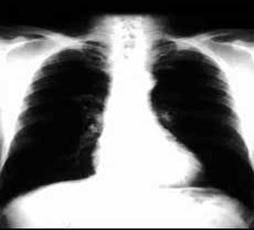

发现肺部阴影后,人们的第一反应就是肺癌,但其实肺部有阴影并不代表着就是肺癌。

肺部阴影并不能与肺癌划等号。

肺部阴影,是指在X线胸片、胸部CT等影像学检查中所发现的片状或肿块影。一般来说,会表现为“肺部阴影”的疾病,除了有肺癌、肺部先天性发育异常之外,比较多见的还有肺部感染性疾病,包括肺炎、肺结核、支气管扩张、肺曲霉菌病等。

医生指出,如果在X线片检查中发现“肺部阴影”,人们不必过分紧张,但应立即去正规医院进行系统的检查。低剂量的胸部CT扫描检查是初步筛查肺癌的最佳办法之一,专业医生会通过影像学检查结果综合患者的症状来判断病情。